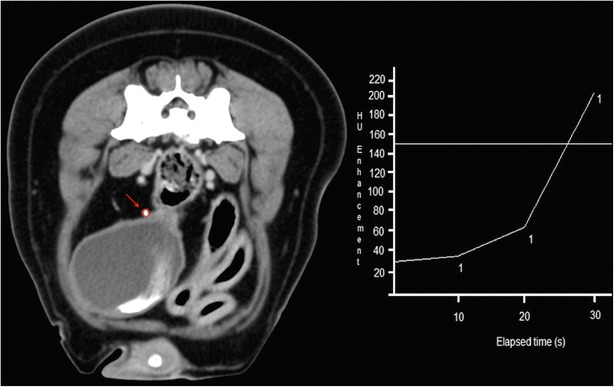

Contrast medium was injected into the patient and a ROI was positioned on the distal third of the ureteral lumen, cranial to the caudo-medial deflection, in order to track the volume of contrast (Fig. 1). CT images were acquired, according to literature, after the 150 HU level was reached into the ROI [14]. During the monitoring phase, low exposure (50 mA) repeated axial scans were performed at the pre-selected level (Fig. 1). By means of a built-in software program a near instantaneous time attenuation curve was generated. When contrast medium reached the desired 150 HU (Fig. 1) the operator triggered a complete helical scan of the caudal abdomen.

Fig. 1.

Transverse image at the level of the distal third of the right ureteral lumen, cranial to the caudo-medial deflection. Positioning of the ROI (red arrow and circle) and tracking of the progressive intraluminal peak enhancement (HU enhancement/elapsed time diagram)